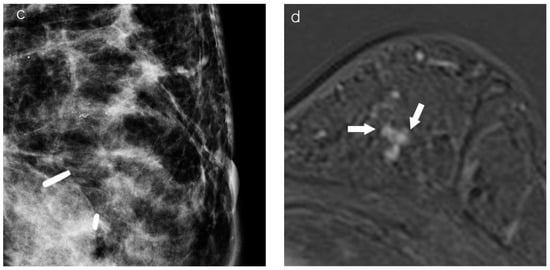

2.3. Assessment of Breast Cancer on Chest CT

2.4. Imaging Analysis

| Tumor presentation | 0.002 | |||

| Mass | 48 (68.6) | 7 (38.9) | 41 (78.8) | |

| Non-mass | 22 (31.4) | 11 (61.1) | 11 (21.2) | |

| Chest CT | ||||

| Background position | <0.001 | |||

| Fatty portion | 44 (49.4) | 5 (16.1) | 39 (67.2) | |

| Glandular portion | 45 (50.6) | 26 (83.9) | 19 (32.8) | |